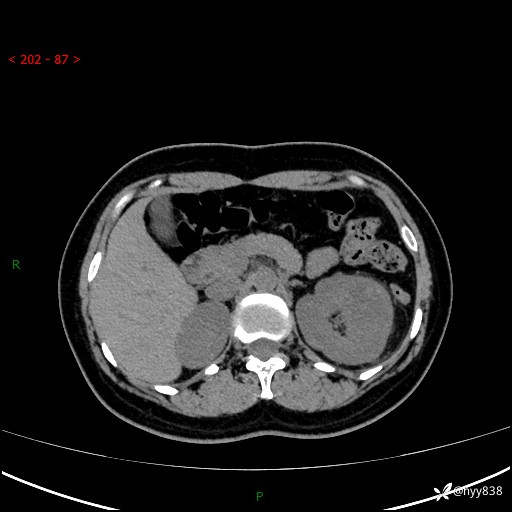

现病史:患者于1周前因左侧腰腹部间断胀痛不适,无恶心呕吐,无明显肉眼血尿,无畏寒发热,无尿频尿急,起病初,患者来我院就诊,查CT提示左肾低密度影,外周血提示:白细胞11.25*10^9/L.行抗感染治疗后未见明显好转,06-18泌尿系增强CT提示左肾类圆形低密度占位(脓肿?肿瘤?),大小:4.0*3.2cm,为求进一步治疗,门诊以“左肾占位”收住我科。 起病以来,患者精神佳,饮食、睡眠良好,大小便正常,体力体重无明显变化。

双肾CT平扫+增强